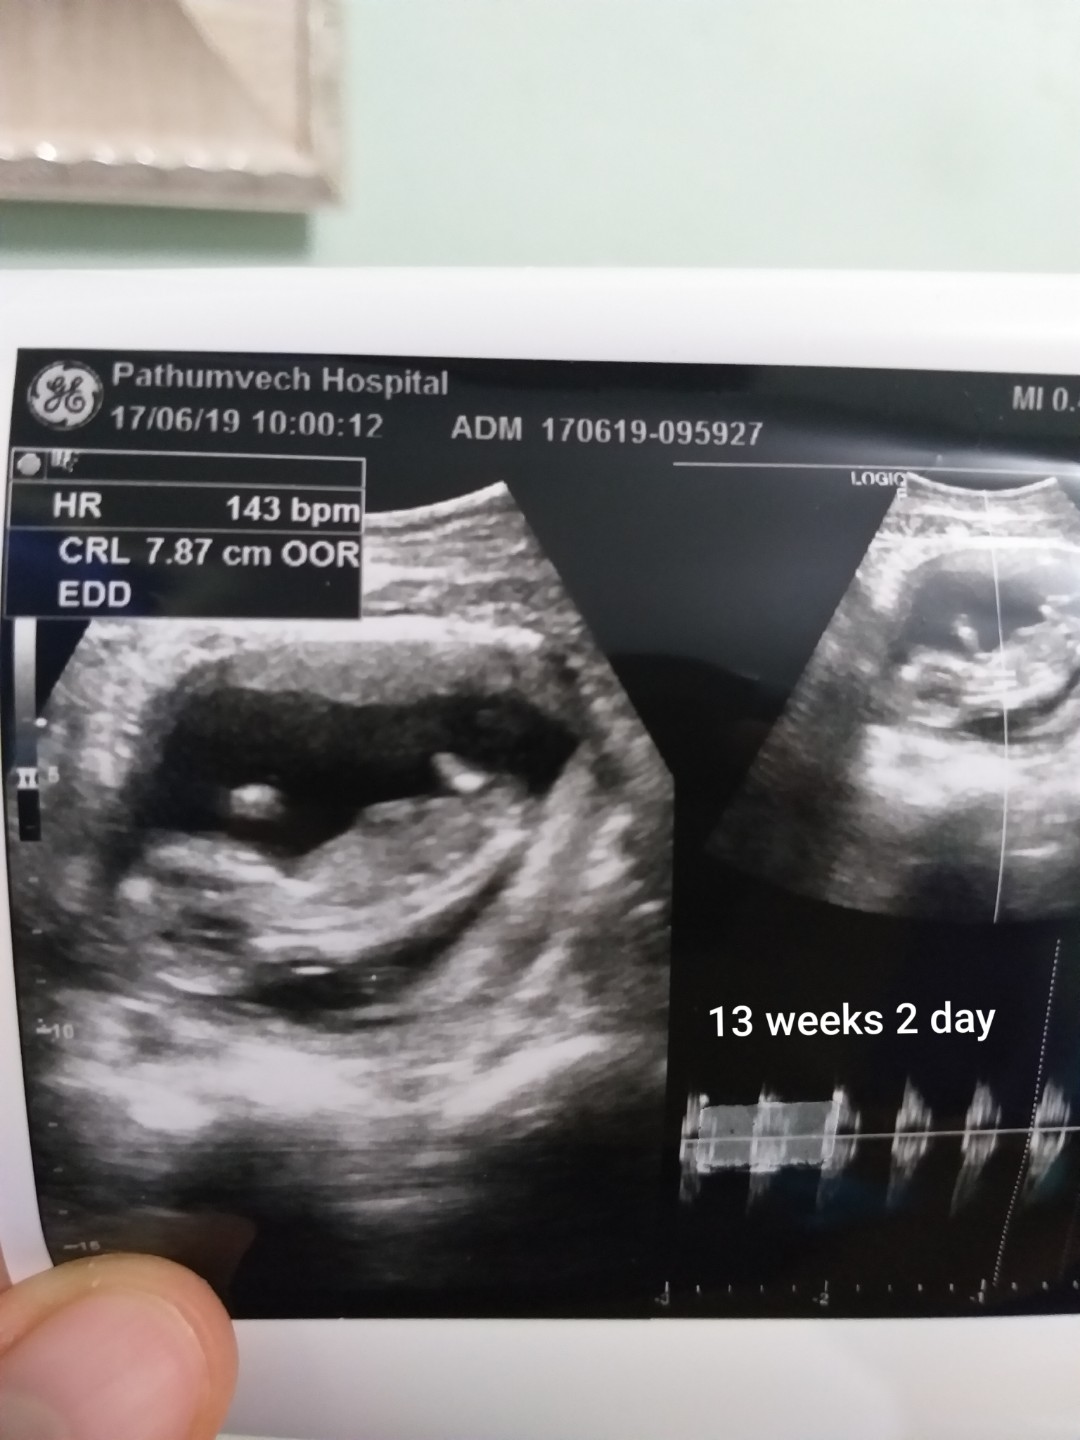

แม่ๆคนไหนมีภาพอัลตร้าซาวด์ประมาณ13วีคบ้างคะ ของเรา13วีค ภาพแบบนี้ค่ะ ดูไม่ออกเลย?

13 w 2 d จ้า